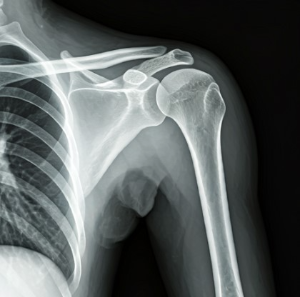

나이가 들어감에따라 몸이 가장먼저 현재 나이를 알려주는 신호를 보내주는 것 같네요. 오늘은 50대 분들의 관절 건강에 대해 이야기해 보겠습니다. 나이가 들면서 우리 몸은 다양한 변화를 겪지만, 특히 관절 건강은 50대부터 각별한 주의가 필요합니다. 관절의 이상은 초기에는 가벼운 불편함으로 시작되지만, 이를 방치하면 만성적인 질환으로 이어질 수 있습니다. 이 글에서는 관절 건강의 중요성과 주의해야 할 증상, 그리고 건강한 관절을 유지하기 위한 필수 운동법과 생활 습관에 대해 깊이 있게 알아보겠습니다.

50대는 관절 건강을 관리하는 데 있어 중요한 전환점입니다. 건강보험심사평가원의 통계에 따르면, 무릎관절증으로 병원을 찾는 50대 환자 수가 40대에 비해 무려 3배 이상 증가한다고 합니다. 이는 단순한 숫자가 아닌 우리 몸이 보내는 경고 신호로 이해해야 합니다.